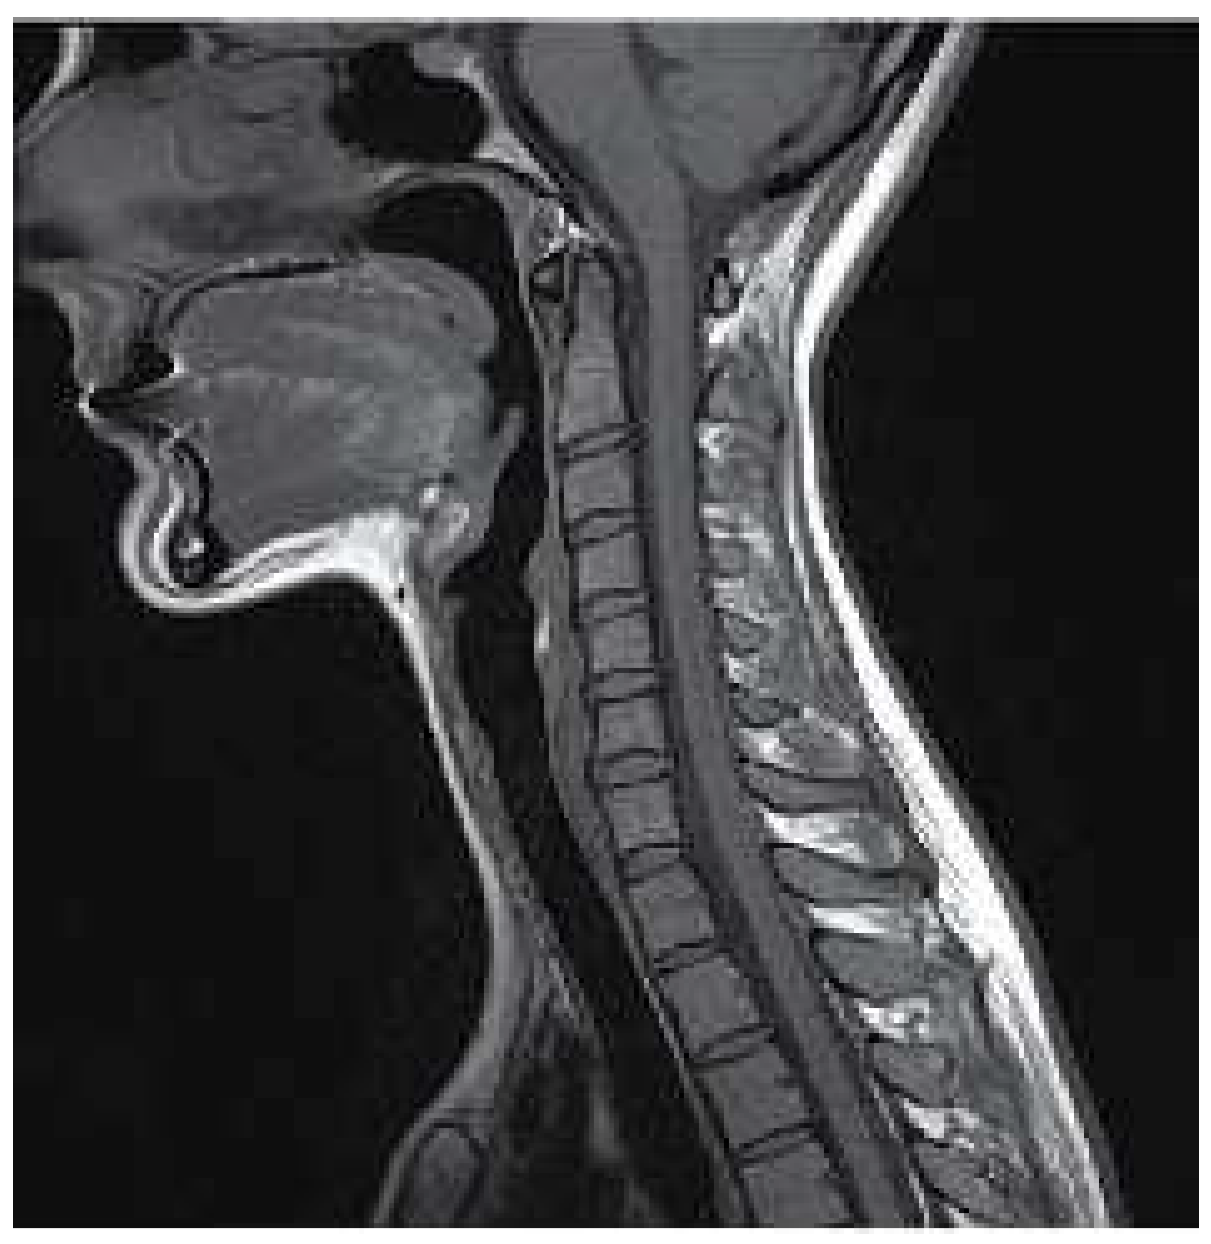

MRI is a non-invasive technique widely used in medicine to obtain medical images needed to make a later diagnosis. This technique is based on the physical phenomenon of resonance; it consist of the transition between different energy states when an atomic nucleus is introduced in an external magnetic field of a characteristic frequency. This frequency, known as Larmor frequency, corresponds to the precession frequency of the protons inside the nucleus. When a magnetic field is applied, the protons absorb the energy and promote to a higher level. Once the magnetic field is removed, the protons decay to the ground state. MRI measures the time and energy released from this last transition. Because of their surroundings, those two values will be different for each proton. Then, by applying the Inverse Fourier Transform to the obtained data it is created the image with different contrast for each component of the body [12], as shown in Figure 1.

Figure 1. Example of MR image of the spinal column [13].